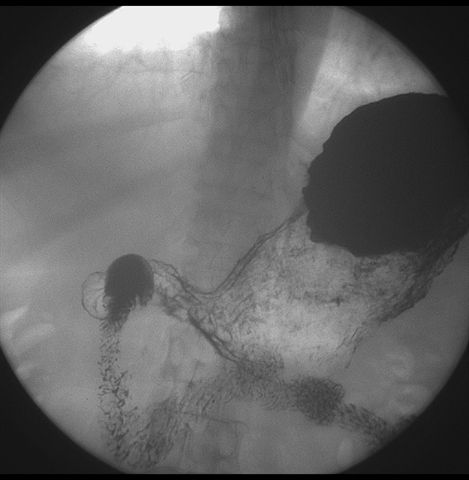

标题: X6872:F,69y,胃部不适。

胃窦至幽门段胃壁僵硬,扩张受限,局部纠集粘破坏,呈杵状。提示溃疡癌变可能性大。

胃窦癌可能性大,建议胃镜活检。钡剂太稀,吃的有点多。

支持考虑胃窦癌可能,胃内滞留液太多,胃窦部僵硬。

瀑布型胃,胃粘膜那是一个乱,窦部充盈不好,第16幅窦部粘膜反倒又很顺,先定个胃炎胃窦炎胃窦癌待排之类,建议进一步作胃镜检查。

胃窦部见钡池影,局部粘膜紊乱,纠集呈杵状改变,胃壁扩张受限,胃窦癌可能性大,建议胃镜检查.

胃窦部管腔扩张度较差,形态略有改变,胃窦粘膜显示欠佳,胃窦部占位可能性大,结合胃镜活检。

北京肿瘤医院胃镜诊断皮革胃。